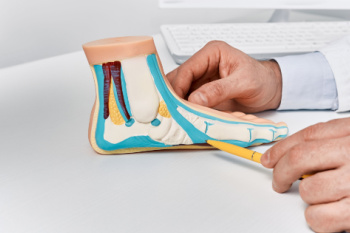

Surgery for Morton's Neuroma

Morton's neuroma, a painful condition characterized by the thickening of tissue around the nerves leading to the toes, can significantly impair mobility and quality of life for those affected. While conservative treatments such as orthotic devices, shoe modifications, and corticosteroid injections can provide relief for some individuals, surgery may be necessary in cases where symptoms persist or worsen over time. Surgical intervention for Morton's neuroma typically involves removing the affected nerve tissue to alleviate pain and discomfort. The procedure aims to release the pressure on the nerves and restore normal function to the foot. Surgeons may opt for various techniques, including nerve decompression or neurectomy, depending on the severity and location of the neuroma. While surgery offers the potential for long-term relief from Morton's neuroma symptoms, it also entails risks and considerations that patients should discuss thoroughly with their podiatrists. If you have developed Morton’s neuroma, it is suggested that you consult your podiatrist who can discuss if surgery is a treatment option for you.

Morton’s neuroma is a very uncomfortable condition to live with. If you think you have Morton’s neuroma, contact Deann Hofer Ogilvie, DPM of Ascend Foot & Ankle Center. Our practitioner will attend to all of your foot care needs and answer any of your related questions.

Morton’s Neuroma

Morton's neuroma is a painful foot condition that commonly affects the areas between the second and third or third and fourth toe, although other areas of the foot are also susceptible. Morton’s neuroma is caused by an inflamed nerve in the foot that is being squeezed and aggravated by surrounding bones.